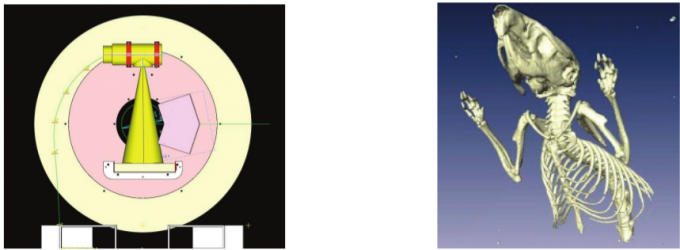

| ABSTRACT |

rSPECT es un nuevo escáner SPECT para animales de laboratorio compuesto por dos gamma-cámaras de elevado rendimiento y tamaño reducido. El diseño de las cámaras, basado en cristales pixelados y tubos fotomultiplicadores, permite el uso de diferentes colimadores en función de los requerimientos del estudio.

This work reports on the development and evaluation of the PET component of a PET/CT system for small-animal in-vivo imaging. The PET and CT subsystems are assembled in a rotary gantry in such a way that the center of rotation for both imaging modalities is mechanically aligned. The PET scanner configuration is based on 2 detector modules, each of which consist of 2 flat-panel type PS-PMTs (Hamamatsu, H8500) and 2 (30 × 30 elements) LYSO arrays.

Este trabajo describe el proceso de desarrollo y la evaluación inicial de un nuevo sistema tomográfico PET/CT de alta resolución, enfocado a la realización de estudios preclínicos “in-vivo” con animales de laboratorio. En el diseño implementado, los centros geométricos de cada modalidad de imagen están alineados mecánicamente permitiendo la obtención de conjuntos de datos con información anatómica y funcional que se registran y fusionan de forma automática.

En este artículo se describe la implementación de un sistema PET/CT basado en un ‘gantry’ común. El subsistema de detección PET está formado por dos detectores enfrentados compuestos cada uno de ellos por dos matrices de cristales de centelleo (MLS) y dos tubos fotomultiplicadores sensibles a posición (H8500). El subsistema CT comprende una fuente micro-focal de rayos X junto con un detector formado por elementos semiconductores. Los elementos que forman el escáner CT, así como los detectores enfrentados del sistema PET han sido situados en el mismo plano, de tal forma que los centros axial y trans-axial son compartidos por ambos sistemas. Para evitar contaminación y ruido en la adquisición, los detectores han sido rodeados con elementos de blindaje.

| JOURNAL | XXIV Congreso Anual de la Sociedad Española de Ingeniería Biomédica, Noviembre 2006 |

Se describe la implementación de un escáner micro-CT adecuado para ser utilizado como elemento complementario en

diferentes escáneres PET para pequeños animales. El diseño básico del sistema se basa en el montaje de un tubo micro-foco de rayos-X y un detector digital plano sobre un soporte rotatorio.

In this work we report initial results from a prototype of a small-animal positron emission tomography (PET)/ computed tomography (CT) system based on a common rotating gantry. The PET system consists of two detector modules based on MLS arrays and four large-area, flat-panel type PS-PMTs. The CT scanner uses a micro-focus X-ray tube and a semiconductor X-ray detector in a cone-beam geometry. Space for opposed PET detectors and the CT scanner has been allocated on the same face of the gantry disk, thus achieving a co-planar geometry that perfectly aligns the trans-axial and axial centers for both image modality systems. Shields around the detectors reduce cross modality contamination due to scatter in the sample when it is illuminated by the X-ray source.